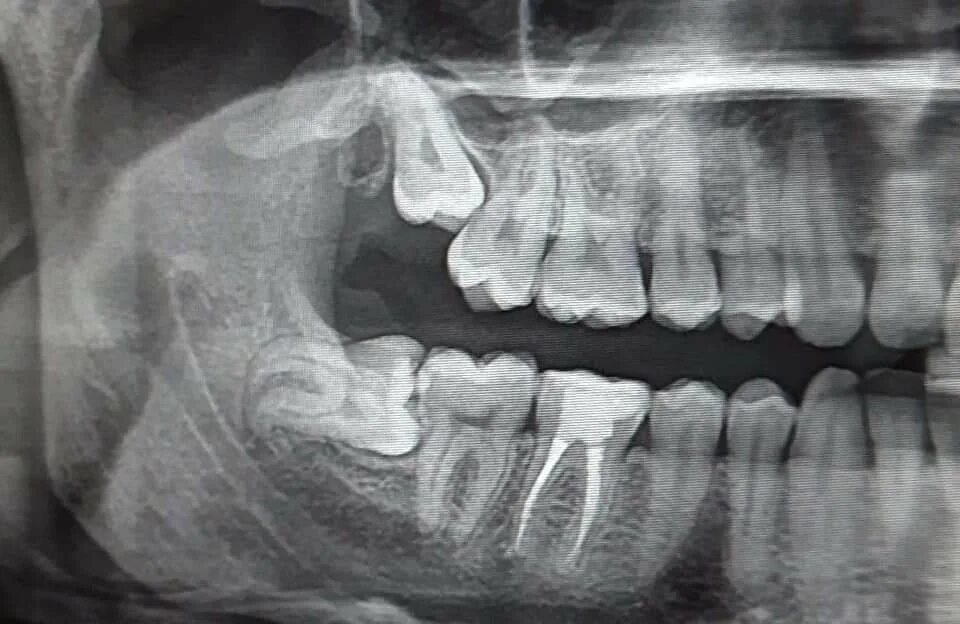

Зубы слева